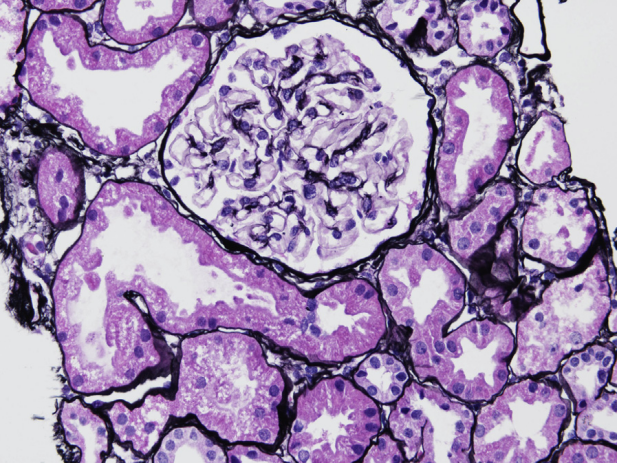

狼疮型肾炎Ⅳ型(弥漫性LN),弥漫性(超过50%)肾小球累及,伴活动性病变。大多数肾小球有轻度系膜区扩张和轻度节段性毛细血管内细胞增生。一个肾小球有明显的节段性细胞增多和小细胞新月体,鲍曼氏膜破裂和坏死延伸到小动脉(PASM染色)

狼疮型肾炎Ⅳ型(弥漫性LN),慢性伴中度间质纤维化、肾小球硬化和纤维细胞新月体,活动伴节段性毛细血管内细胞增生(PAS染色)。